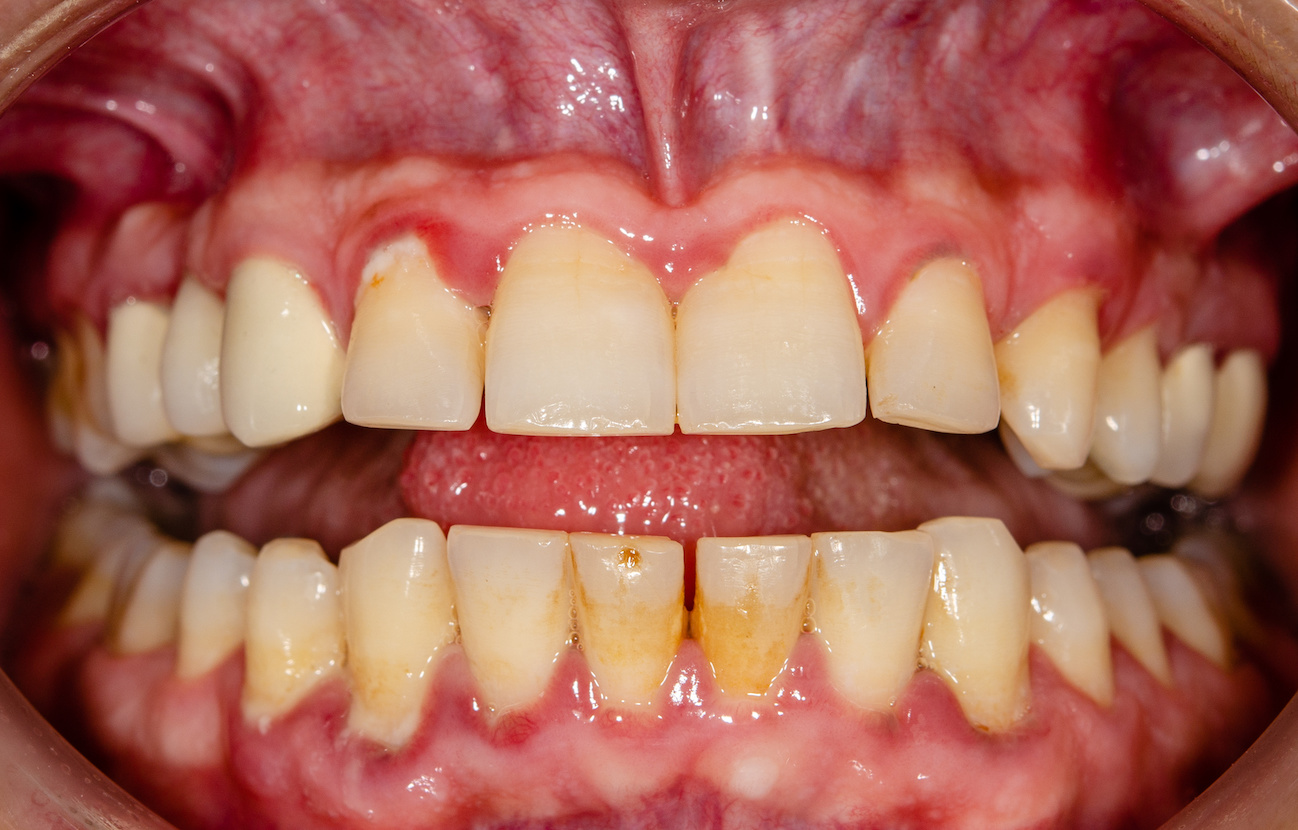

歯茎の腫れや出血

歯周病は初期の段階から、歯茎の腫れや、歯磨きの際に出血しやすくなるなどの症状が現れます。重度にまで進行すると、通常は引き締まっている歯茎が、触るとぶよぶよとした感触になり、腫れが慢性化して歯を磨いていなくても自然に出血することもあります。

また、歯と歯茎の隙間から膿が出たりして、痛みや不快感が発生することもあるでしょう。

歯茎が下がる

細菌による炎症が歯を支える組織である歯槽骨に到達すると、歯槽骨が破壊され歯を支える骨の量が減少します。それにより歯茎が通常よりも下がり、歯が長く見えるなどの症状が起きるのです。

歯周病が初期の段階では、歯茎が下がったと感じることはほぼ無いため、歯茎が下がった、歯が長くなったと感じた時には歯周病はかなり進行している状態でしょう。